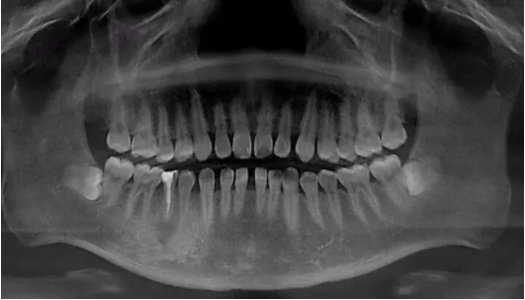

关于牙齿矫正

很多人都有此困惑

年龄不会影响牙齿矫正

年龄不是问题

1.矫正牙齿可以选择隐形矫正和不戴牙套矫正。

2.矫正牙齿,不仅没有年龄限制,还很便宜!